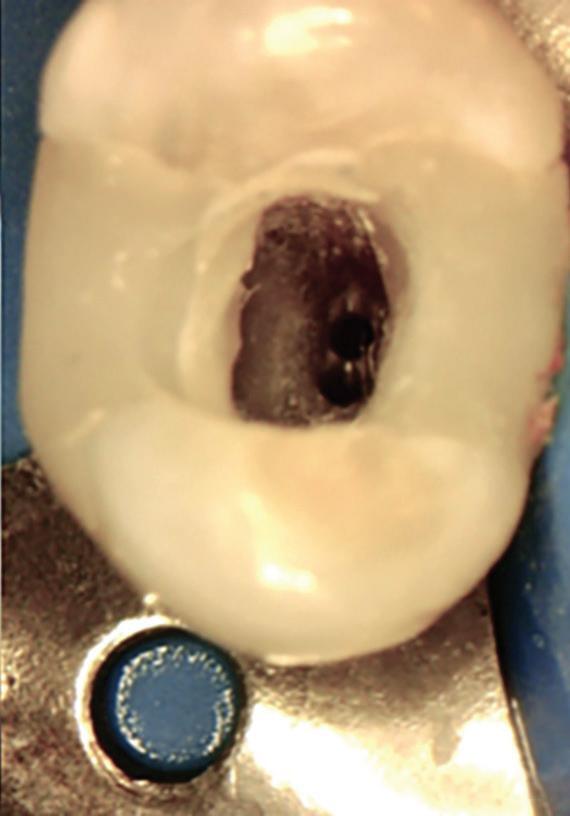

Fig. 19-1. Paciente idoso submetido a tratamento endodôntico (dente 25). (a) Canais atresiados (visualizados na radiografia periapical.) ( bliteração da entrada do canal vestibular. (d) Canal localizado e ampliado (uso de microscopia e ultrassom). ( a